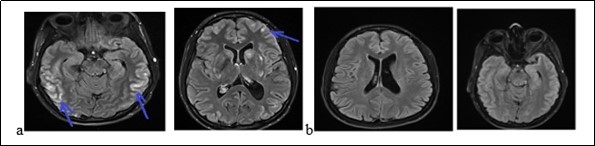

Mrs. A.S., a woman of 56, was admitted to hospital on february 9, 2018 for gradual onset in a three week, confusion, intense and diffuse headache with vomiting and photophobia. She treated the headache in automedication with a non-steroidal anti-inflammatory drug (NSAID, ibuprofen). The symptoms had worsened after 3 weeks with a serious trouble as her environment noted it. She had no story of vascular pathology. The neurological examination noted a neck stiffness, trouble and mutism. On the cardiovascular examination, the blood pressure was of 210/90 mm Hg. The examination of the other organs was normal. The blood count showed a leukocytosis at 12600 / mm3. The serum creatinine, glycemia, thyroid hormones and blood ionogram were normal. The cerebrospinal fluid (CSF) revealed 27cells/mm3 predominantly neutrophilic, with a normal glycorachia and hyperpropteinorachia of 0.6g/l. There was no germ in CSF after the preparations. The initial brain MRI (Figure 2a) had shown a range of edema in the left occipital lobe and diffuse enhancement of the leptomeninges. The electroencephalogram (EEG) had shown some slow waves in the left occipital lobe, with no epileptic figure or encephalopathy. The patient had been treated with nimodipine (60 mg every 8 hours) associated with analgesic drugs. The trouble and headache had decreased. The brain MRI (Figure 2b) at one (1) month had shown a complete decrease of the germs. The clinical and imagery findings fell on diagnosis of RPE syndrome.

Figure 2.Cerebral MRI showing a left occipital edema and a diffuse contrast enhancement of the leptomeninges (a) with complete decrease of the lesions after treatment (b)